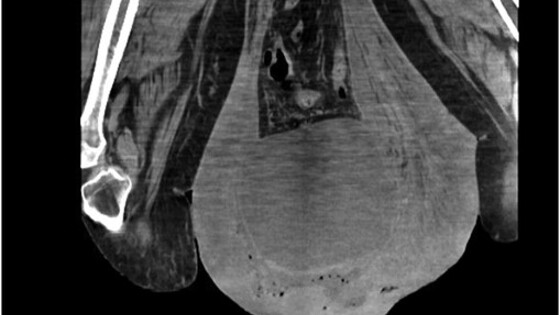

Конечным диагнозом стала гангрена Фурнье — быстро прогрессирующая гангрена мошонки с высоким риском летального исхода. Хирурги экстренно прооперировали мужчину, отдельной проблемой было добраться до «утонувшего» в мошонке пениса, чтобы поставить катетер. На следующий день операцию пришлось повторить, удалив еще часть омертвевшей ткани. Также мужчине были назначены антибиотики.

Перевязки на протяжении следующих пяти дней оказались настолько болезненными, что врачи решили удалить мошонку полностью. Затем они также провели операцию по уменьшению грыжи. Спустя 4 недели мужчина успешно восстановился после операций.